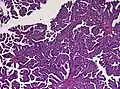

The tumor is neuroectodermal in origin and similar in structure to a normal choroid plexus. They may be created by epithelial cells of the choroid plexus. Papillary fronds lined by bland columnar epithelium are visible under the microscope. Normal absences include mitotic activity, nuclear pleomorphism, and necrosis.[10] Tumors have positive immunohistochemistry for cytokeratin, vimentin, podoplanin, and S-100.[11] Up to 20% of choroid plexus papilloma patients may test positive for glial fibrillary acidic protein (GFAP).[12] Studies have found that fourth ventricle cancers express more S100 than lateral ventricle tumors, and older patients (over 20 years) express more GFAP and transthyretin than younger patients.[13] Some individuals with choroid plexus papilloma have germline TP53 gene mutations, according to genetic analyses.[14] These cancers rarely exhibit nuclear p53 protein positivity. Aicardi syndrome, hypomelanosis of Ito, and 9p duplication are syndromic correlations of choroid plexus papilloma.

Micrograph of a choroid plexus papilloma. H&E stain.

Plexuspapillom Detail

Plexuspapillom Overview